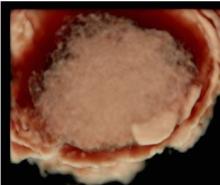

In seguito a questo grande impegno che sta continuando con il reclutamento di nuovi centri e di nuovi casi, ormai vi è in letteratura una forte evidenza che la valutazione soggettiva di una massa ovarica effettuata da un operatore dedicato attraverso l'ecografia sia un ottimo metodo per discriminare tra benignità e malignità ed in molti casi può essere suggerita pure una corretta diagnosi di natura della neoplasia sulla base della sola ecografia che, se associati alla clinica, all'esecuzione dei marcatori ovarici, aumentano ulteriormente la sensibilità nella diagnosi e nella stadiazione preoperatoria.

I progetti in essere prevedono l'esecuzione di ecografie ginecologiche di II livello di un operatore dedicato, atte a discriminare tra patologia benigna e maligna ovarica secondo la caratterizzazione della massa con i dati dello IOTA.

L’expertise dell’operatore, associato all’acquisizione da parte dell’Istituto di un’apparecchiatura di alto livello, dotata di software di ultima generazione anche con 3D e 4D, permettono di caratterizzare nei minimi dettagli l’eventuale presenza di patologia ovarica e di verificare l’eventuale disseminazione limitrofa agli organi circostanti. Questo da una parte dovrebbe permettere di evitare di misconoscere o sottovalutare alcune patologie ovariche potenzialmente evolutive in senso maligno e pertanto da indirizzare a trattamento chirurgico, e dall'altra di condurre un follow-up ecografico ad alcune patologie ovariche definite benigne secondo criteri standardizzati e ampiamente validati atti ad evitare una chirurgia non necessaria. Nel gruppo di lavoro IOTA infatti si è visto in questi anni che quasi l'80 percento delle masse ovariche operate risultavano benigne. E’noto che ogni procedura chirurgica è associata a possibili complicanze a breve come a lungo termine.